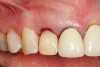

Fig 11. Four months after healing, a final crown was placed. An esthetically pleasing outcome was achieved.

Figure 11